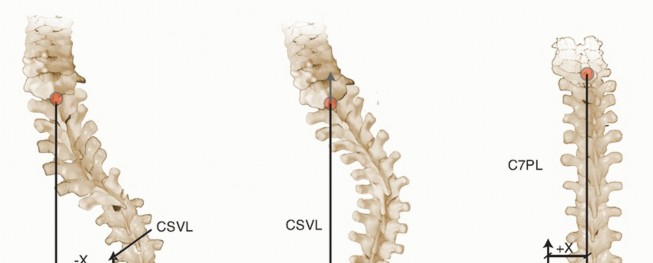

Coronal balance: the relationship between the C7 plumb line and center of S1 on PA views (FIG 4)

FIG 4 • Coronal balance is evaluated on the standing PA radiograph. A virtual plumb line is dropped from the center of C7. The lateral distance between that plumb line and the center of S1 is then measured. (Left to right) Negative coronal decompensation, coronal compensation, and positive coronal decompensation. CSVL, center sacral vertical line.

FIG 4 • Coronal balance is evaluated on the standing PA radiograph. A virtual plumb line is dropped from the center of C7. The lateral distance between that plumb line and the center of S1 is then measured. (Left to right) Negative coronal decompensation, coronal compensation, and positive coronal decompensation. CSVL, center sacral vertical line.